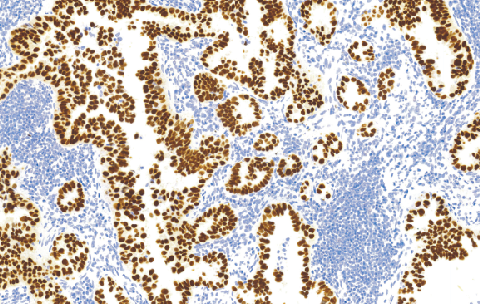

Thyroid Transcription Factoc-1(TTF-1)鼠抗人甲状腺转录因子(TTF-1)单克隆抗体

甲状腺转录因子-1(TTF-1)是同源结构域转录因子家族的一个成员,在甲状腺、肺和脑组织中起着调节基因表达作用。据报道TTF-1在超过90%的肺小细胞癌,75%肺非小细胞癌中表达,但典型的肺类癌中TTF-I不表达。TTF-I还表达在甲状腺乳头状滤泡癌和甲状腺肿,(一种非恶性及非毒性甲状腺肿)但在间变性甲状腺癌中TTF.1不表达。

- 阳性部位:胞核

- 适用组织:石蜡切片

- 预处理:热修复